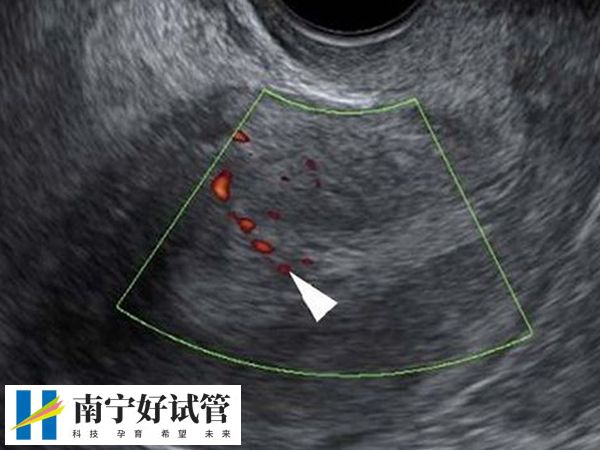

如果女性身体情况较好,术后没有明显不适,且恢复较快,可以在取卵后第二天进行复查。只是要注意,如果身体恢复较慢或有不适症状,建议在术后第三天再返院复查。对于取卵数目较多的患者,建议在术后5-7天内再复查B超,以评估卵巢恢复情况。